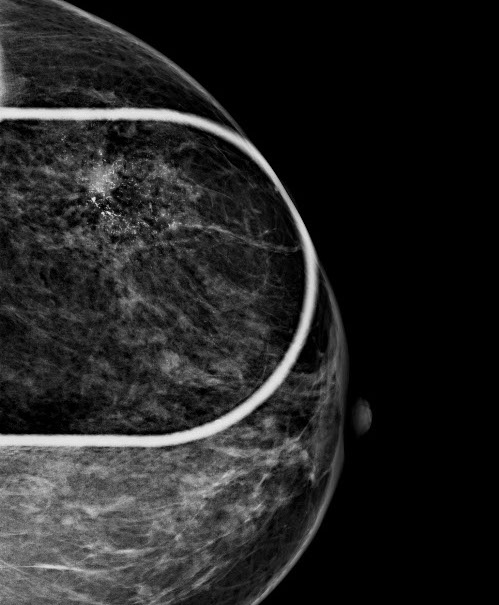

3.  Exaktere Bildanalyse – sicherere Diagnose

Durch die höhere Kontrastauflösung bei einem höheren Kontrast-Rausch-Verhältnis wird die Erkennungsrate von malignitätsverdächtigen Veränderungen deutlich verbessert. Der Radiologe kann auf hochauflösenden 5 MP-Monitoren die Dichte, Form und Kontur von Gewebearealen wesentlich exakter differenzieren und so gutartige von bösartigen Herdbefunden sicherer unterscheiden. Im Speziellen sind Mikroverkalkungen auch bei der dichten Brust besser zu analysieren.

Die Diagnosesicherheit und Möglichkeit einer Brustkrebsfrüherkennung durch die Mammographie, hängt von der Dichte des Brustdrüsengewebes ab. Einteilung der Dichtegrade wurde vom American College of Radiology (ACR) übernommen.

Bei einem Dichtegrad 3 sinkt die Sensivität der Mammographie deutlich, bei Dichtegrad 4 liegt sie unter 50 %. Durch gleichzeitigen Einsatz der Ultraschalluntersuchung wird die Sicherheit in der Diagnoseerstellung jedoch wieder auf

ca. 90 % angehoben.